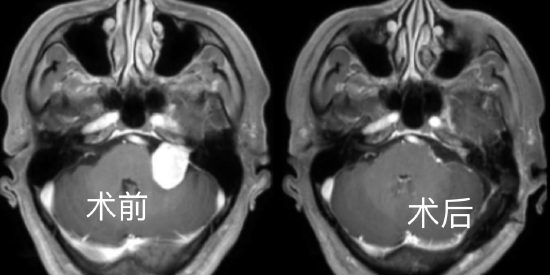

患者是44岁的李师傅,来之湖北红安县的工人,前2年发现听力下降,伴有耳鸣,当时未予以重视。就诊当地医院发现巨大右侧囊实性听神经瘤,大小约4*3.3*4.2cm。肿瘤压迫控制呼吸、心跳的“生命中枢”脑干,后来出现右侧肢体无力,右侧肢体肌力约4级。近日住入该院后,神经疾病诊疗中心王煜教授,神外金胜昔教授团队科学论证手术方案,再麻醉科胡玲教授团队精心护航下,历经7小时完整切除肿瘤,术后恢复良好,术后病理证实为听神经鞘瘤。